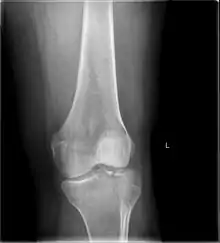

A severe tibial plateau fracture with an associated fibular head fracture

A tibial plateau fracture is a break of the upper part of the tibia (shinbone) that involves the knee joint.[1] Symptoms include pain, swelling, and a decreased ability to move the knee.[1] People are generally unable to walk.[2] Complication may include injury to the artery or nerve, arthritis, and compartment syndrome.[1]